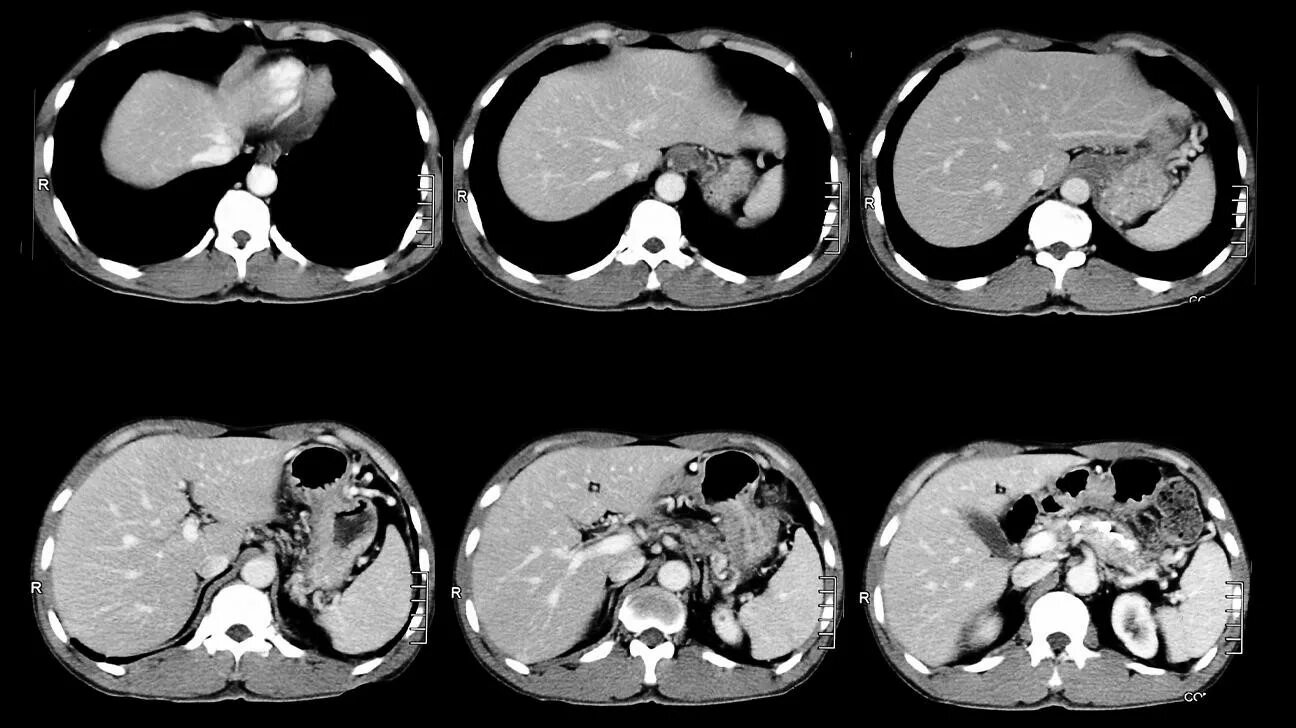

Можно делать кт через месяц